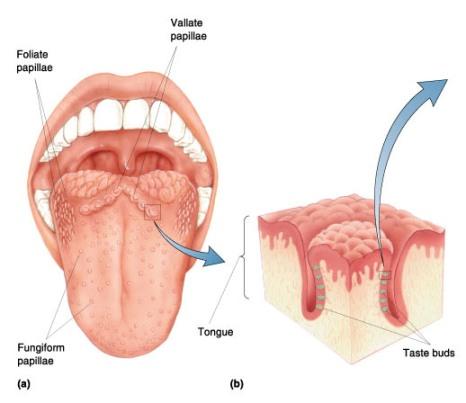

Taste bud

28

Frenulum

29

Papullae

30

Filiform

Papillae

31

Fungiform

Papillae

32

Circumvallate

Papillae